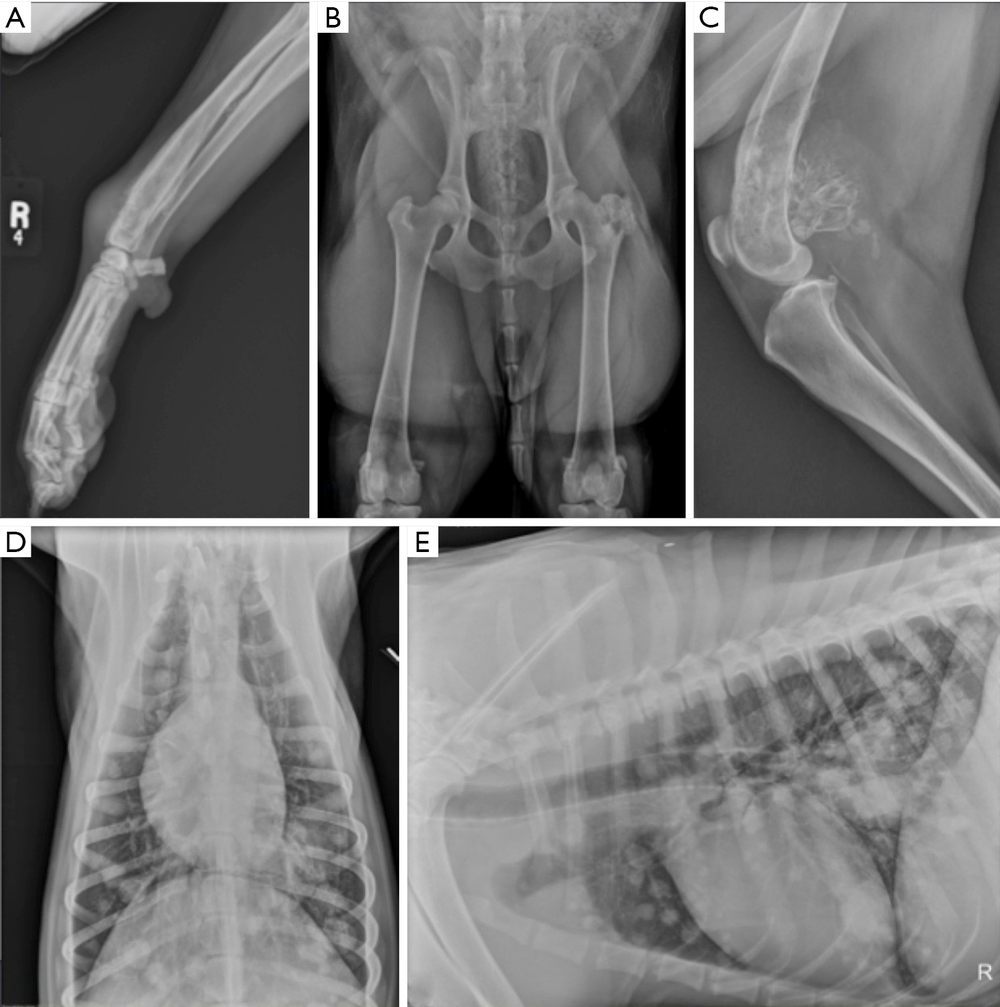

Most work-ups start with a physical exam and orthopaedic x-rays of the affected limb. Radiographs can show patterns of bone destruction and new bone formation that raise strong suspicion for a bone tumour.1

Because infections and some other conditions can occasionally mimic parts of this picture, confirmation commonly involves collecting a sample from the lesion. A bone biopsy is one accepted way to do this, and your vet may recommend referral so it can be done as safely and accurately as possible.1, 2

Staging is about looking beyond the painful bone to understand what else might be happening in the body. This usually includes imaging of the chest because the lungs are a common site of metastasis, plus additional tests depending on the dog and the planned treatment pathway.1, 2